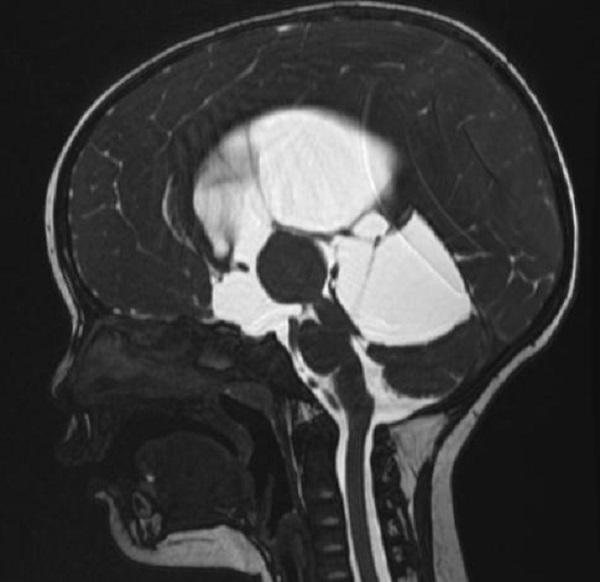

一岁多的赫赫小朋友自出生头颅就比同龄小孩大,近半月来进食后出现呕吐,伴头痛,在当地医院及省内多家医院治疗不见好转,于是来到二一五医院神经重症监护室,因患儿近半月多不能正常进食,入院时精神萎靡,头颅MRI检查提示“脑室系统扩大,双侧脑室额角周围间质水肿,左侧丘脑占位病变,鞍上池及小脑上池扩大”。

为进一步鉴别脑积水类型,行磁共振3D FIESTA序列检查可见侧脑室扩大明显,中脑导水管中段阻塞、三脑室底受压下陷,诊断梗阻性脑积水。

手术历时60分钟,先后成功完成了第三脑室底造瘘、脑室内脉络丛电灼术、左侧丘脑肿瘤切除术及ommaya囊植入术,术中出血不多,达到了真正的内镜微侵袭治疗,术后患儿可正常进食,无呕吐,头痛等症状均得到了缓解,目前正在进一步康复治疗中。